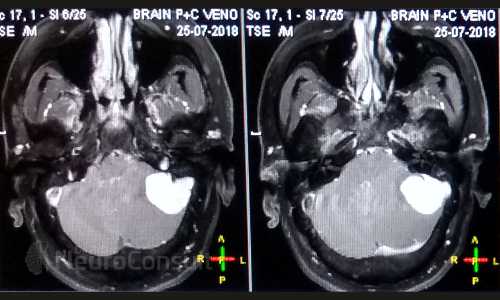

My Cases Studies & Work